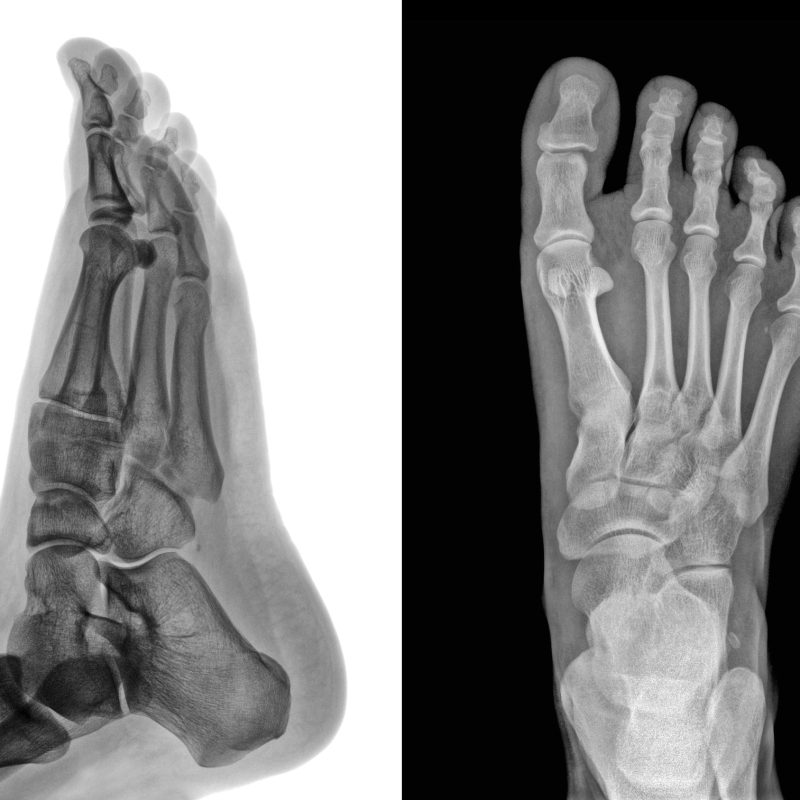

Al hablar de Ortopodología, hacemos referencia a los tratamientos podológicos efectuados en el pie y que se realizan de forma no quirúrgica, es decir, con elementos externos que una vez personalizados, compensan posturas, devuelven la función elástica perdida, redistribuyen presiones, evitan deformaciones y evitan posibles lesiones.

Intentando dar solución a patologías como pies planos en niños, fascitis en corredores, lumbalgias y un largo etc.

roentgenogram

Son tratamientos que ya no van al milímetro, ahora nos ajustamos a micras de la morfología del pie y después de más de dos años podemos decir que los resultados son una gran evolución respecto al resto de tratamientos.